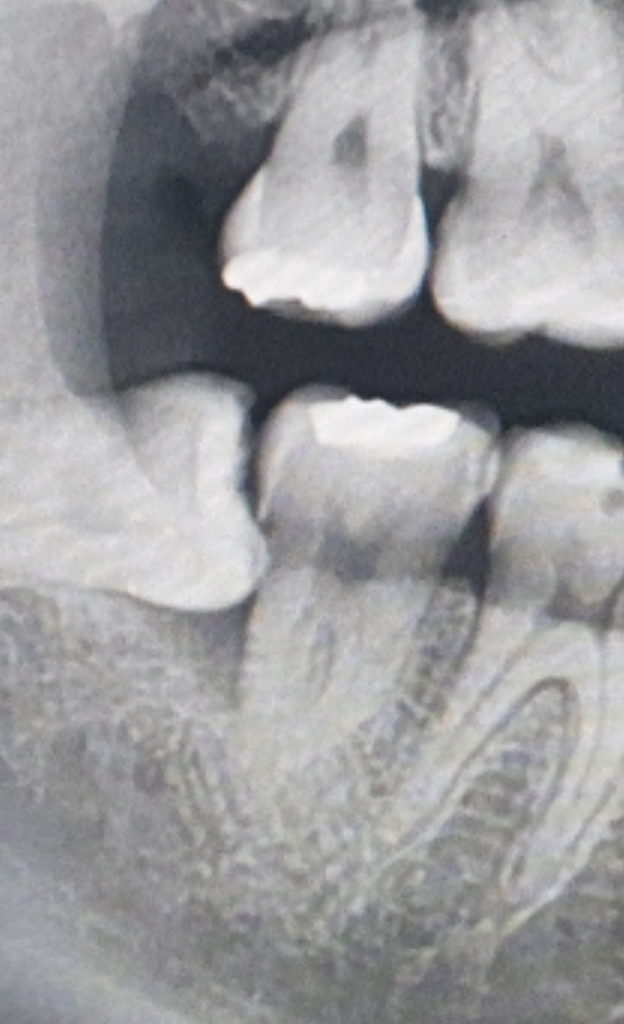

치아에 금이간건 증상으로 알수 잇지만, 사진상으로만 봐도 사랑니 앞니가 많이 썩어 보입니다 .신경치료를 하셔야될것같습니다.

해당사진으로는 판별하기 힘듭니다. 금이 가 있는 경우 신경치료 및 크라운치료가 필요하며 예후 불량시 발치의 가능성도 있습니다